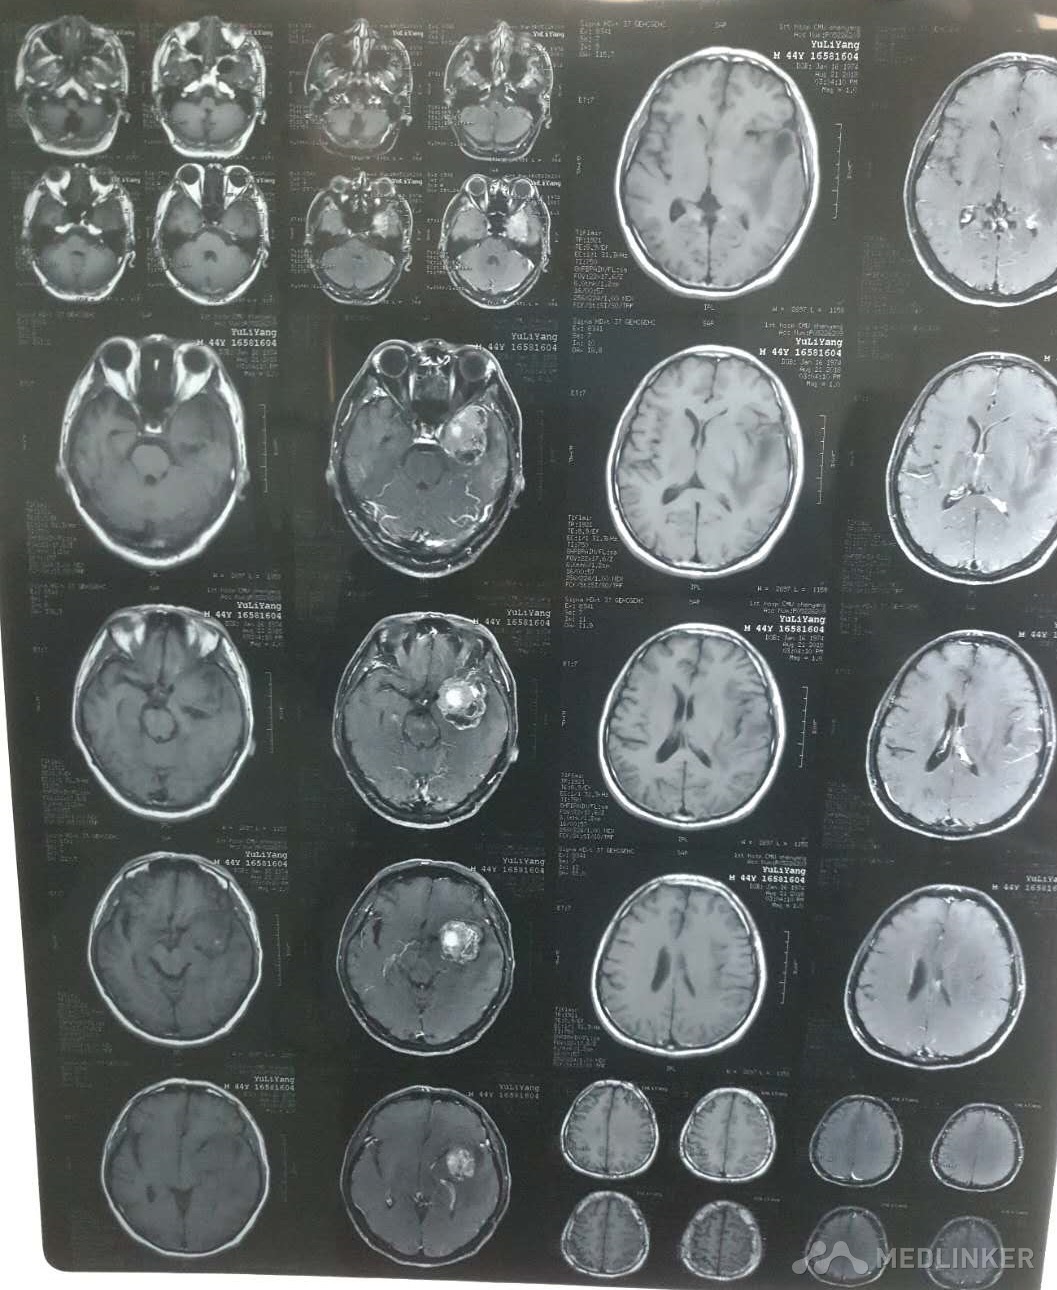

左侧颞叶占位

颞叶肿瘤

主诉:肢体抽搐1天 现病史:患者于昨日在睡眠中出现肢体抽搐,呼之不应,具体表现为双眼上翻,牙关紧闭,口吐白沫,双上肢及躯干先屈曲后反张,无舌咬伤,无尿失禁,约持续4分钟后症状缓解,10分钟后意识转清,醒后患者自觉头痛,全身酸痛,无法会议之前发生的事情,于我院急诊行CT检查,示左侧颞叶占位病变,给予患者止抽等对症支持治疗,为求进一步诊治入院,急诊以“颅内占位性病变"收治。 既往史:一般健康状况:良好          药物过敏史否认          传染病史:否认肝炎结核病病史 预防接种史:按计划          手术外伤史:否认          输血史:否认        疾病史:高血压10余年、脑栓塞 (曾接受磷酸肌酸钠治疗) 个人史:出生地—         迁徙史:无 冶游史:无         嗜烟嗜酒:无         职业及工作环境:无烟尘、无毒物及放射性物质接触史         婚姻史:结婚年龄:适龄岁 配偶健康状况:良好 其他:无  家族史:父亲:已故,    母亲:已故,               子女:健康 兄弟姐妹:健康               家族遗传病史:否认               家族中传染病史:无

初步诊断:左侧颞叶占位,高血压,脑栓塞 确定诊断:左侧颞叶占位,高血压,脑栓塞 治疗:大脑深部病损切除术